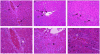

Earlier studies conducted by our laboratory have shown that suppression of transforming growth factor-beta (TGFbeta)-mediated upregulation of connective tissue growth factor (CTGF) by iloprost resulted in a greatly diminished oval cell response to 2-acetylaminofluorene/partial hepatectomy (2AAF/PH) in rats. We hypothesized that this effect is due to decreased activation of hepatic stellate cells. To test this hypothesis, we maintained rats on a diet supplemented with 2% L-cysteine as a means of inhibiting stellate cell activation during the oval cell response to 2AAF/PH. In vitro experiments show that L-cysteine did, indeed, prevent the activation of stellate cells while exerting no direct effect on oval cells. Desmin immunostaining of liver sections from 2AAF/PH animals indicated that maintenance on the L-cysteine diet resulted in an 11.1-fold decrease in the number of activated stellate cells within the periportal zones. The total number of cells proliferating in the periportal zones of livers from animals treated with L-cysteine was drastically reduced. Further analyses showed a greater than fourfold decrease in the magnitude of the oval cell response in animals maintained on the L-cysteine diet as determined by immunostaining for both OV6 and alpha-fetoprotein (AFP). Global liver expression of AFP as measured by real-time PCR was shown to be decreased 4.7-fold in the L-cysteine-treated animals. These data indicate that the activation of hepatic stellate cells is required for an appropriate oval cell response to 2AAF/PH.